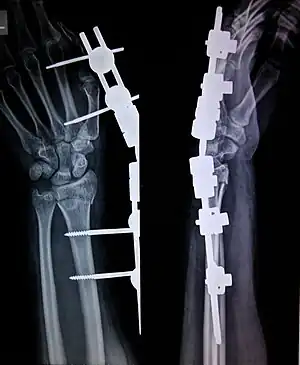

External fixation is a surgical treatment wherein Kirschner pins and wires are inserted and affixed into bone and then exit the body to be attached to an external apparatus composed of rings and threaded rods — the Ilizarov apparatus, the Taylor Spatial Frame, and the Octopod External Fixator — which immobilises the damaged limb to facilitate healing.[1] As an alternative to internal fixation, wherein bone-stabilising mechanical components are surgically emplaced in the body of the patient, external fixation is used to stabilize bone tissues and soft tissues at a distance from the site of the injury.

In this kind of reduction, holes are drilled into uninjured areas of bones around the fracture and special bolts or wires are screwed into the holes. Outside the body, a rod or a curved piece of metal with special ball-and-socket joints joins the bolts to make a rigid support. The fracture can be set in the proper anatomical configuration by adjusting the ball-and-socket joints. Since the bolts pierce the skin, proper cleaning to prevent infection at the site of surgery must be performed.